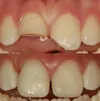

Zirconium Applications

Porcelain Applications

Laminate Veneer